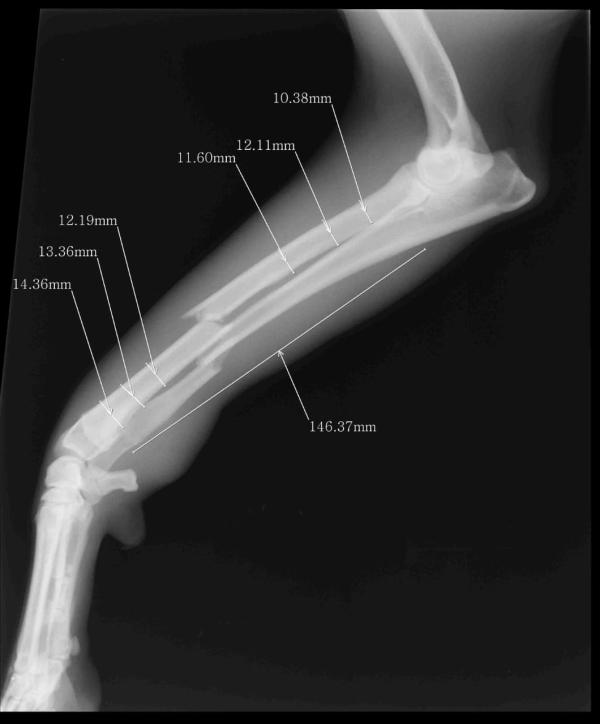

Hola! Mi perrita, una cachorra pastor alemán de 9 meses, que acababa de ser castrada, fue chocada violentamente por un vehículo y le produjo fractura de tibia y peroné desplazada

Las fracturas a nivel de la escápula son poco frecuentes y son asociadas a traumatismos por atropellos. Las fracturas más frecuentes en miembros torácicos son a nivel de húmero y radio cúbito, que pueden lesionarse por infinidades de accidentes, desde arrollamientos hasta caídas.